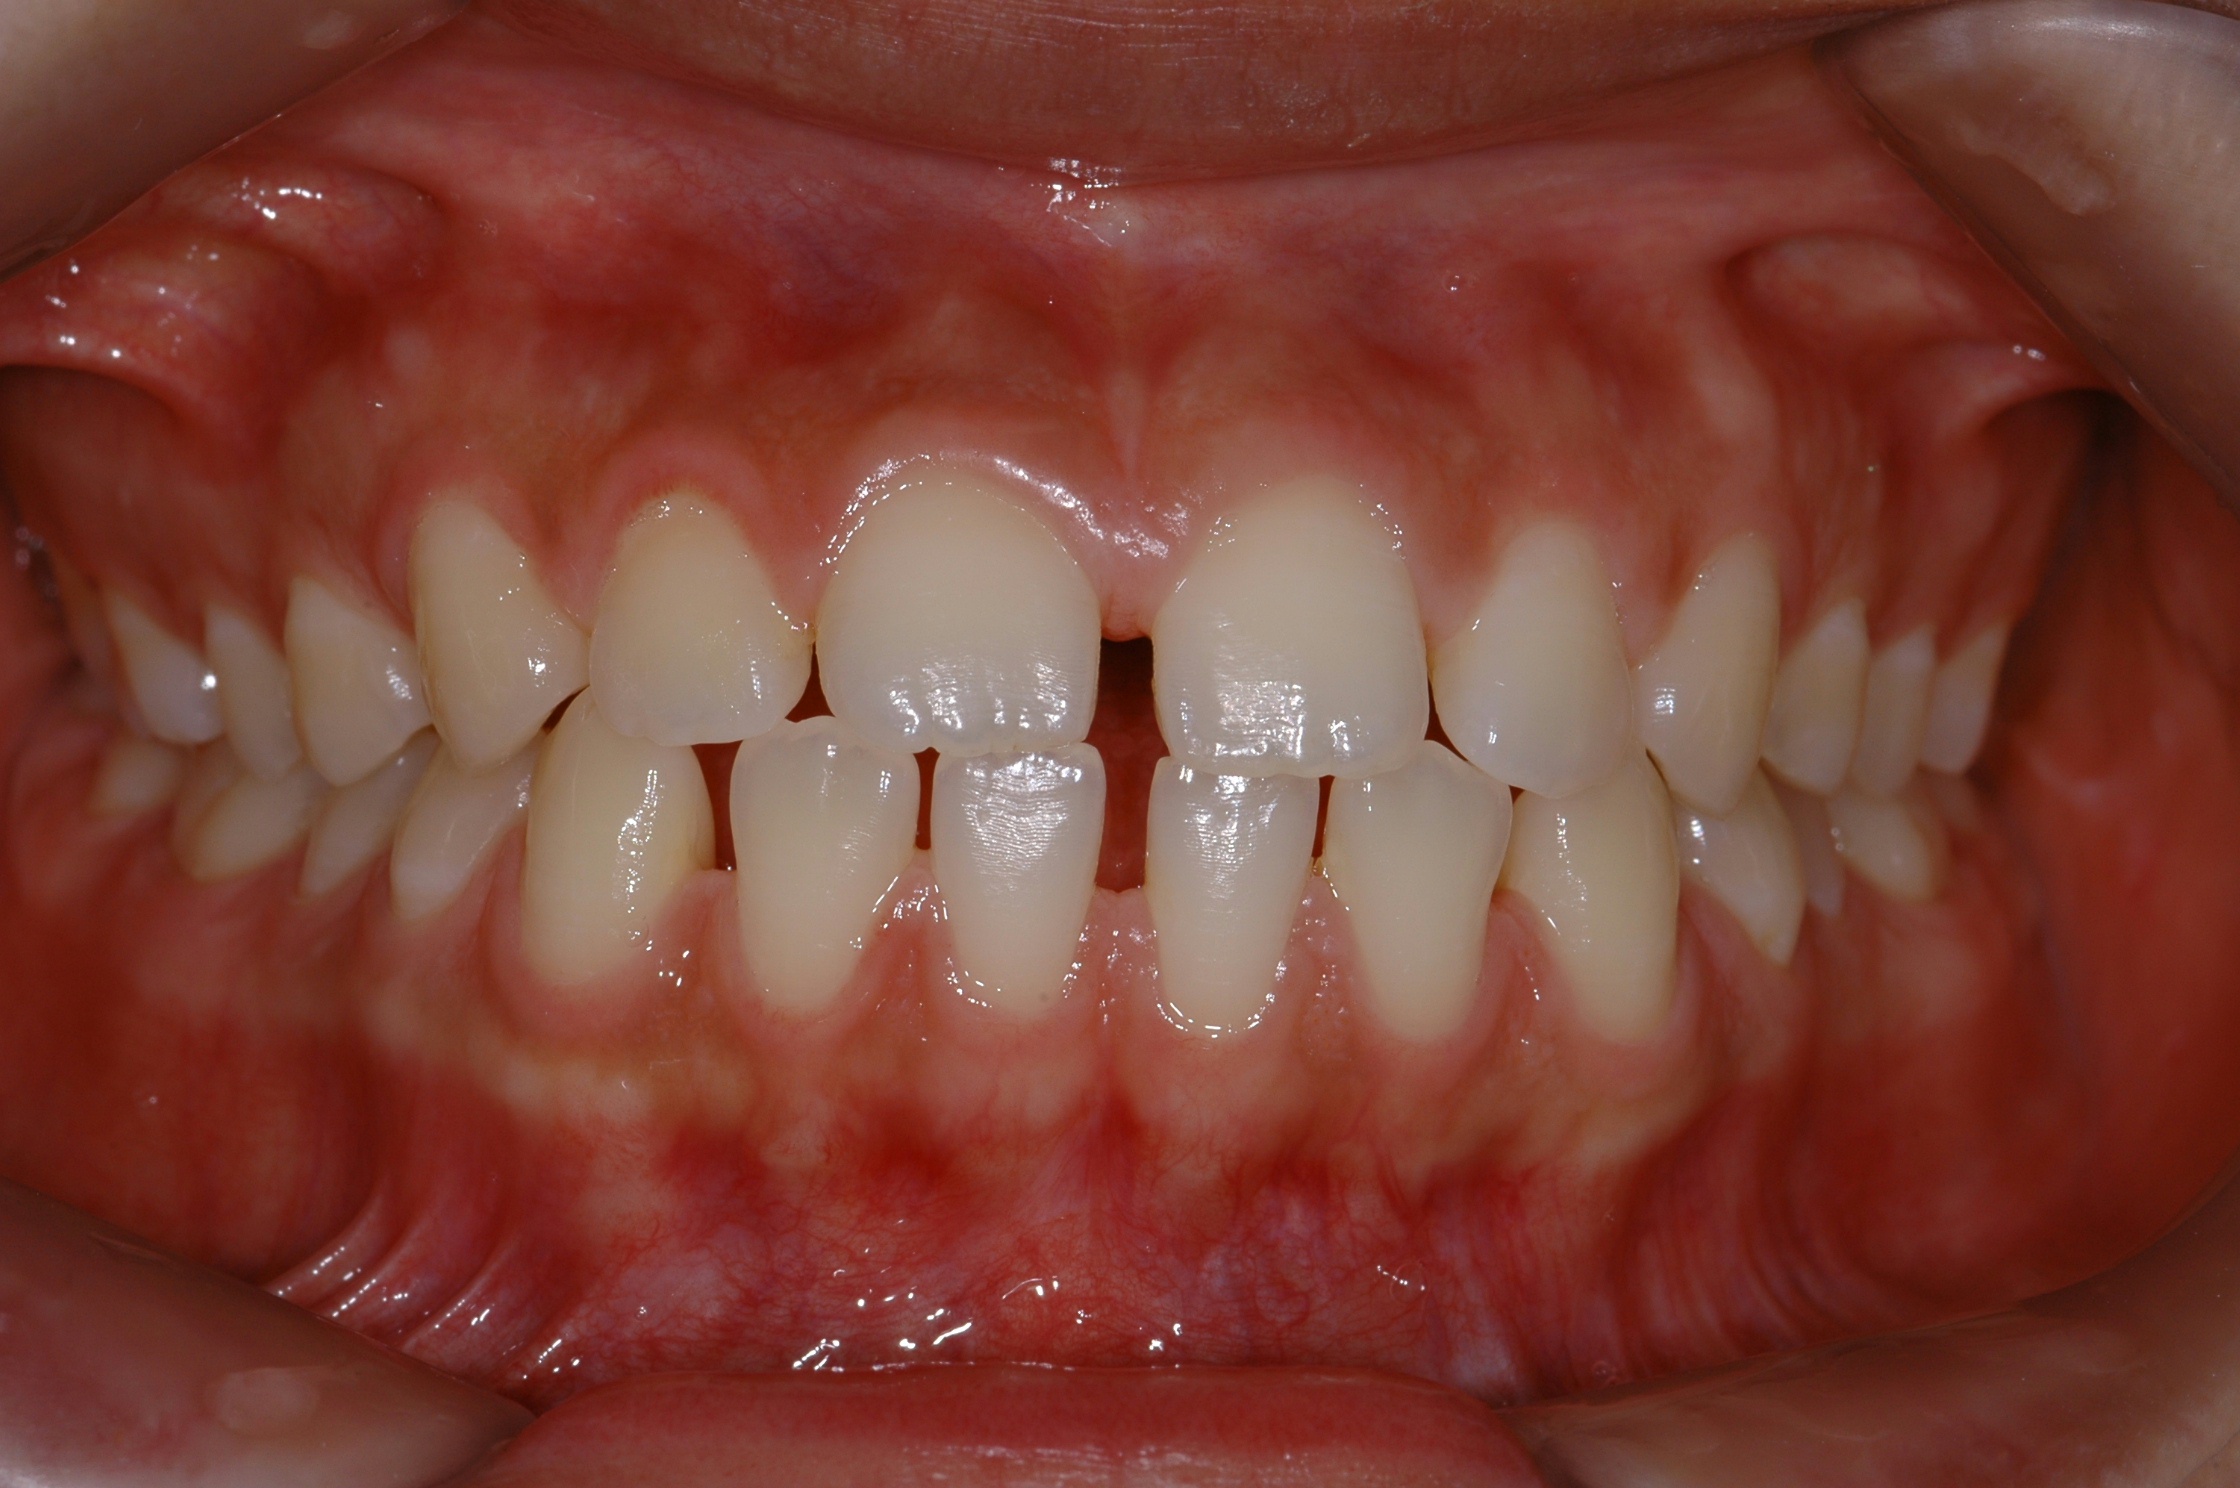

치료 전 사진입니다.